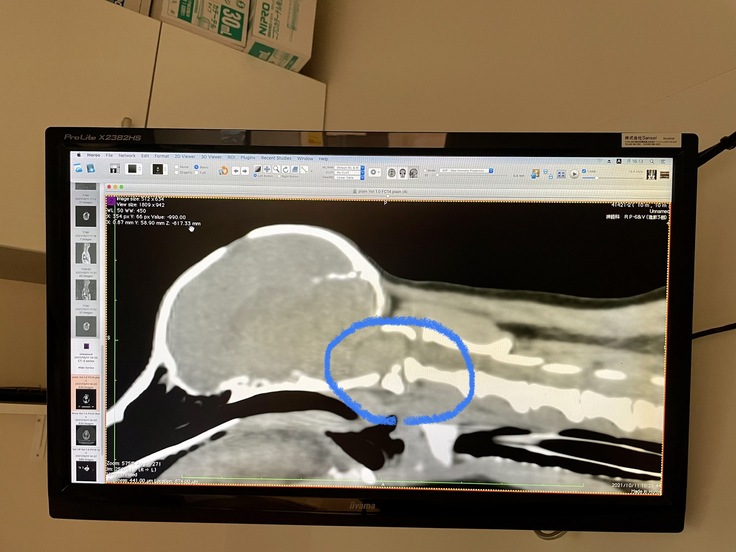

やはり環軸椎不安定症で間違いないとのことでした。このような先天性の病気の子は他にも合併症が多いようですが幸いノアは合併症は見当たらず、そこだけは救いです。

青い丸の部分が通常は真っ直ぐに繋がっていますがノアはガクッと外れているのがわかりますよね。

このガクッとした部分にピンを入れてセメントで固める手術が今回ノアを救うための手術となります。

神経が通っている危険な場所なのでかなり難しい手術になるとは思います。